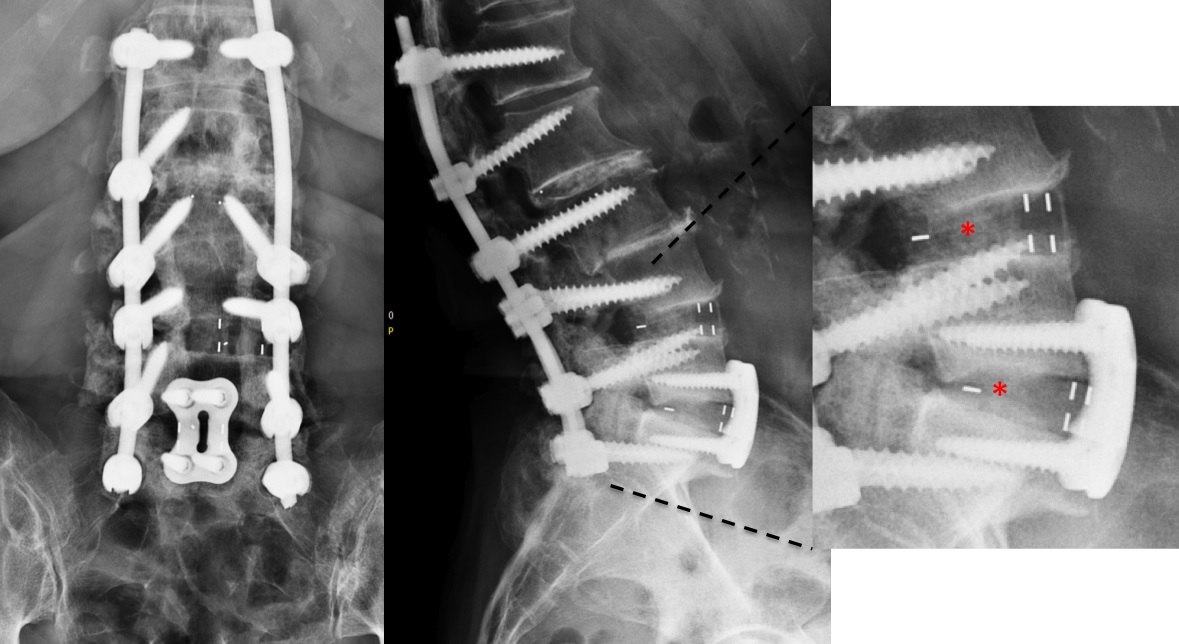

The preoperative standing image of the lumbar spine revealed a flat back with no obvious degeneration of the adjacent segment L1/L2 (Fig 6ab). The implants seemed regularly placed. After wide laminectomy, the spinal canal was open over the whole lumbar spine, illustrated on the MRI scan (Fig 6c).

A CT scan allowed a more detailed assessment (Fig 7). There was an obvious nonunion at L5/S1, with loose screws in the sacrum (red circle). Furthermore, there was instability at L4/L5 as the intervertebral disc presented with an important vacuum phenomenon (asterisk). Foraminal stenosis at L5/S1 (not shown) seemed to be the reason behind the persistent leg pain.

The treatment plan was an anterior height restoration and fusion of L5/S1 and L4/L5. A posterior revision surgery was not considered due to the wide decompression and obvious scar formation. For the correction of level L4/L5, an oblique anterolateral approach (OLIF) was selected due to considerable calcification of the aorta and the iliac vessels. At the L5/S1 level, a straight anterior approach was selected and an additional plate fixation (ATB) was performed.

At level L5/S1, a large cage with an angulation of 14 was selected and for L4/L5, a large cage with an angulation of 10 was placed. In order to perform a fusion, the cages were each filled with 6 mg of BMPII.

From six months postoperatively, leg discomfort decreased. Within an additional four months, pain disappeared completely and both foot and hip weakness recovered. The back pain persists to a certain extent but is not impedingthe patient in her daily activities. The x-ray taken 10 months after the anterior revision surgery revealed a complete and solid fusion on both levels (Fig 8). This is confirmed by the appearance of dense bone in the radiolucentcage.